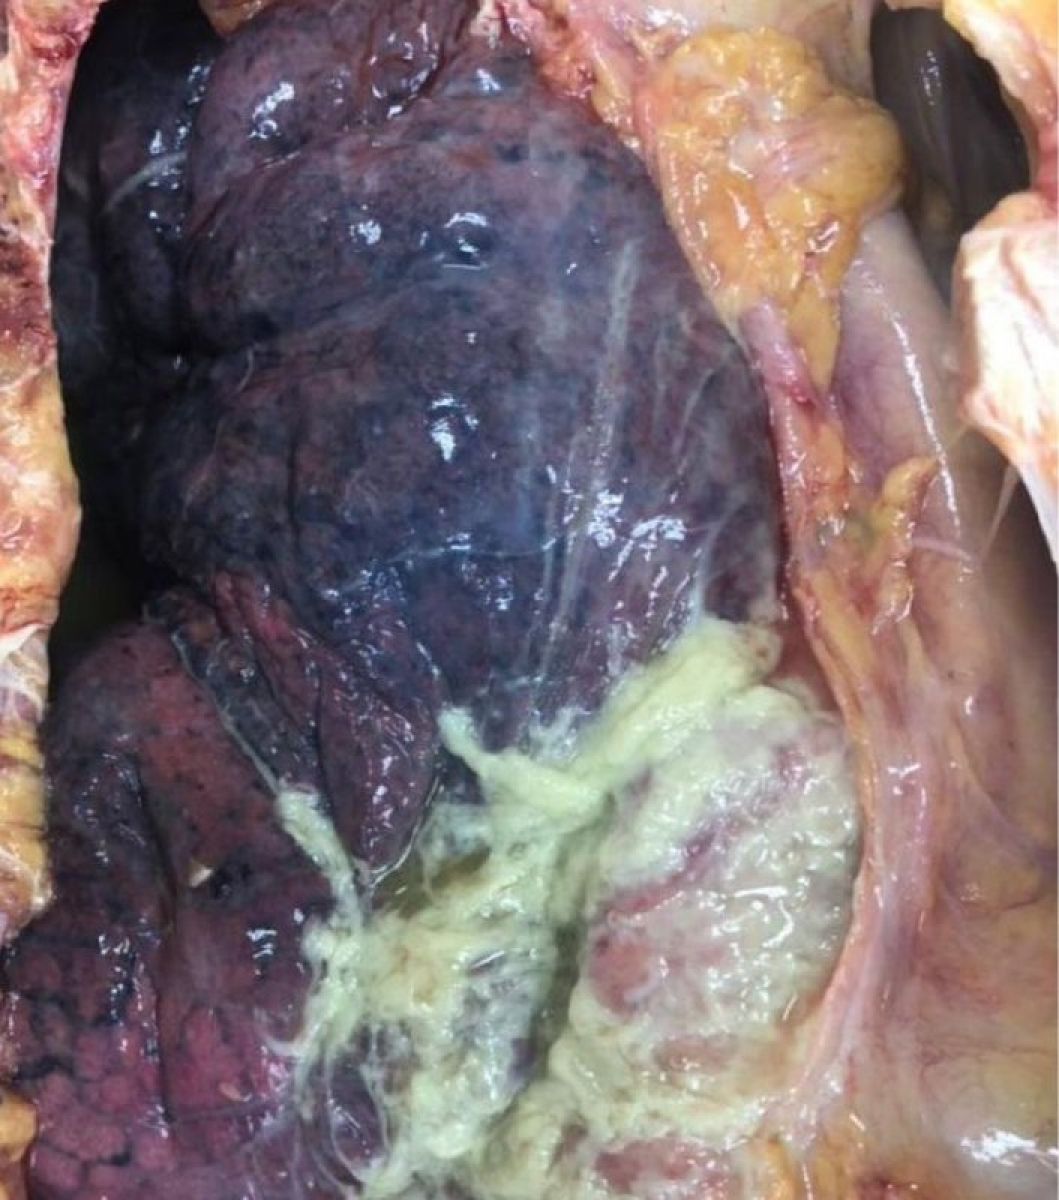

«Это дыхательная недостаточность из-за обширного поражения легочной ткани и нарушения газообмена. Сепсис и септический шок вследствие распространения инфекции в кровоток. Осложнения, такие как абсцесс легкого, эмпиема плевры, гангрена легкого. Полиорганная недостаточность (нарушение функции нескольких органов, например, почек, сердца) как следствие тяжелого воспаления и интоксикации. На вскрытии умершего от внебольничной пневмонии могут обнаруживаться очаговые или долевые инфильтраты в легких, признаки деструкции ткани (абсцессы, гангрена), плеврит или эмпиема плевры, признаки сепсиса или септического шока при тяжелом течении», – объяснил специалист.

(18+) Фото: Легкое человека. Правосторонняя нижнедолевая фибринозно-гнойная пневмония. Правосторонний фибринозно-гнойный плеврит.